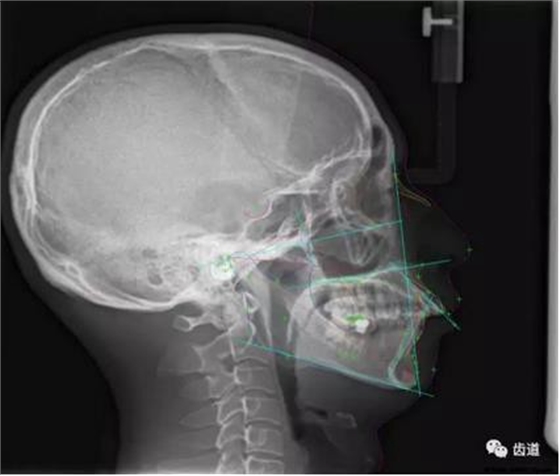

CBCT在頜骨正畸科方面的應(yīng)用:軟件功能的強(qiáng)大,提供有效的數(shù)據(jù),為頜骨正畸提供了極大的幫助,免除了很多臨床醫(yī)生的手工繪圖,并有利于科研、教學(xué)等方面發(fā)展研究。

投影測(cè)量側(cè)位片影像

軟件產(chǎn)生CEPH圖像注釋,不含X線射線圖像